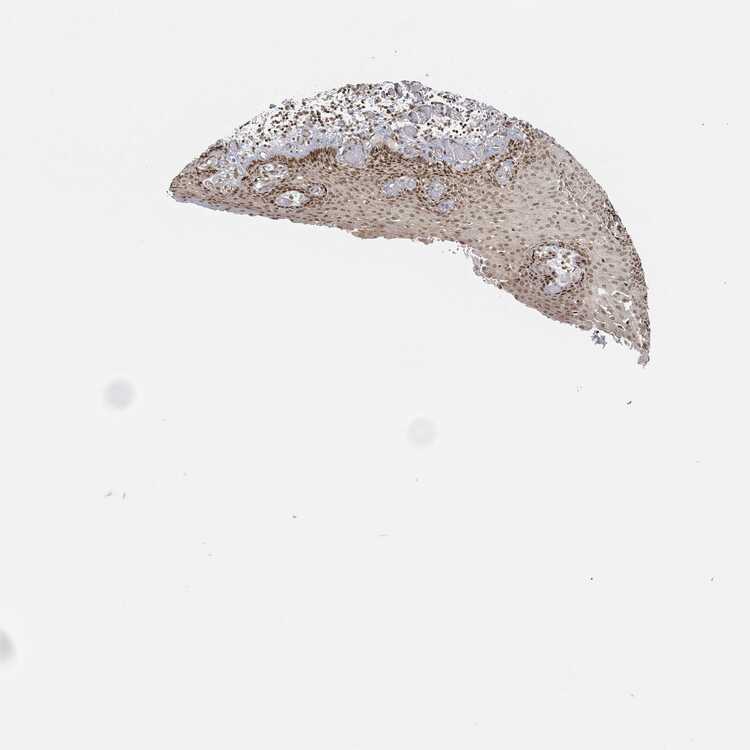

ESOPHAGUS - Antibody stainingi

Antibody staining in the annotated cell types in the current human tissue is reported as not detected, low, medium, or high, based on conventional immunohistochemistry profiling in selected tissues. This score is based on the combination of the staining intensity and fraction of stained cells.

Each image is clickable and will lead to virtual microscopy that enables deeper exploration of all samples and also displays staining intensity scores, fraction scores and subcellular localization as well as patient and tissue information for each sample.

Antibody HPA042413Antibody HPA074310Antibody CAB012991

Squamous epithelial cells LowMediumMedium